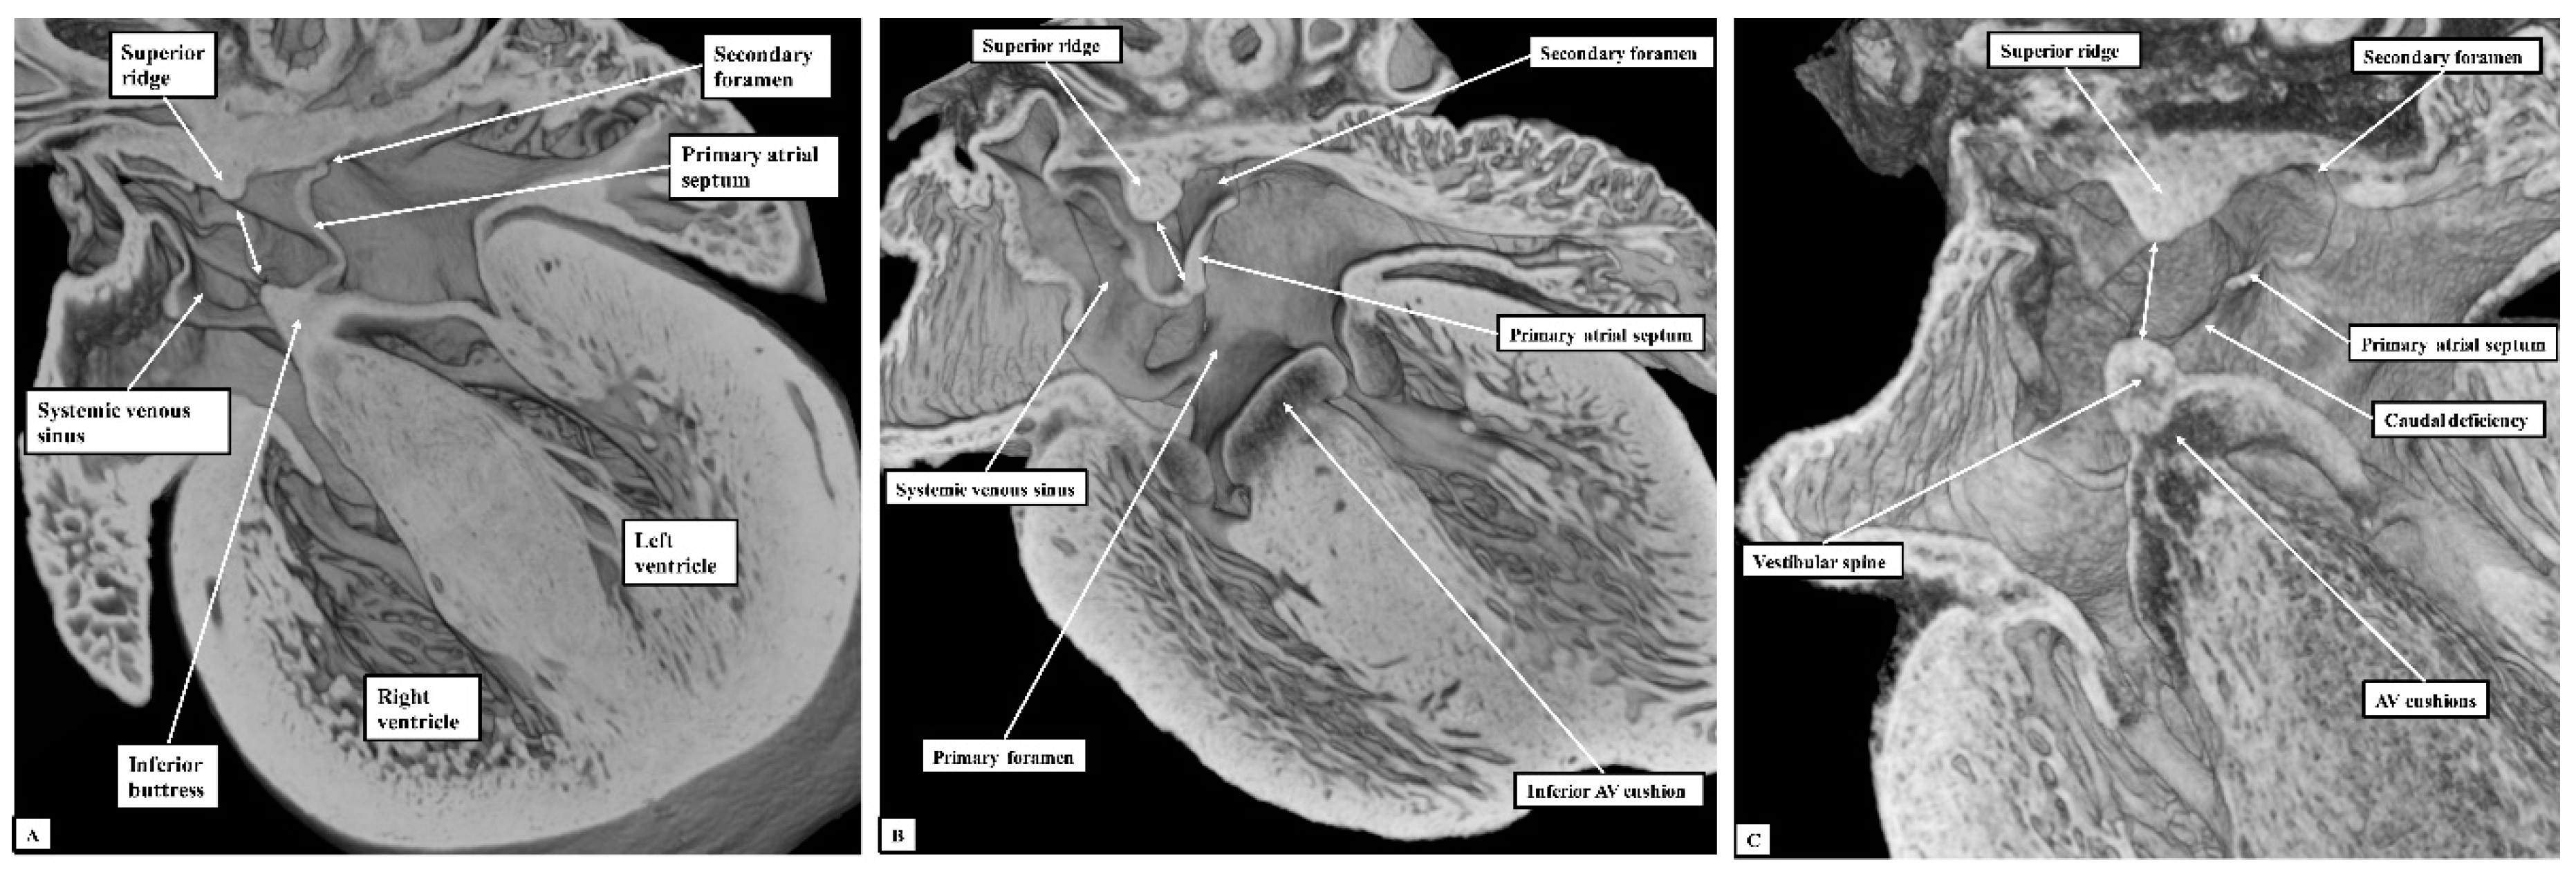

If development proceeds in a normal fashion, the margins of the oval fossa are intact by E15.5. We examined episcopic datasets prepared from 48 mouse embryos at this stage. In 38 of the mice, the findings show the normal arrangement, with the primary septum folded on itself cranially, its length being considerably greater than the length of the fossa (Figure 6A). In these 38 datasets, the vestibular spine and mesenchymal cap fused together to form the caudal rim of the fossa, with obliteration of the seam initially seen between the two components during E13.5 (Figure 5D). The primary septum now forms the floor of the oval fossa, with the space between its cranial margin and the atrial roof forming the oval foramen, or secondary atrial foramen. The excessive length of the septum relative to the dimensions of the fossa provides the mechanism that permits closure of the foramen subsequent to birth. In 10 of the datasets prepared from mice sacrificed at E15.5, however, we found deficiencies of either the inferior rim of the oval fossa, or the attachment of the leading edge of the primary septum. In two, the findings could be attributed to the failure of formation of the vestibular spine (Figure 6B), with additional failure of growth of the primary septum in one of the two. In both, the lack of growth of the spine was associated with persistence of a common atrioventricular junction, with the atrioventricular cushions fused to each other, and also to the crest of the muscular ventricular septum, in other words producing an “ostium primum” defect. In four further datasets, although the vestibular spine had protruded in anticipated fashion to form the caudal margin of the oval fossa, thus separating the right and left atrioventricular junctions and forming the caudal rim of the fossa, the primary septum itself was deficient adjacent to the caudal rim, thus producing a hole in the floor of the fossa adjacent to its antero-inferior buttress, in other words, an “ostium secundum” defect (Figure 6C) The defect was large in two of the datasets but smaller in the remaining two. In the remaining four datasets, the mesenchymal cap had failed to fuse with the vestibular spine. The spaces in the floor of the oval fossa in these four hearts (Figure 7), therefore, are directly comparable to the vestibular defects found in our autopsied hearts.

Figure 6. The images show sections prepared in the four-chamber plane from mouse embryos sacrificed at the sixteenth day of development (E15.5). (Panel A) shows the normal arrangement, with the primary atrial septum forming the floor of the oval fossa (double-headed white arrow). (Panel B) shows an “ostium primum” defect, with common atrioventricular junction due to failure of formation of the vestibular spine. (Panel C) shows a large defect in the primary septum adjacent to the vestibular spine, thus producing a caudal defect within the oval fossa. The double-headed white arrow shows the margins of the oval fossa. AV—Atrioventricular.